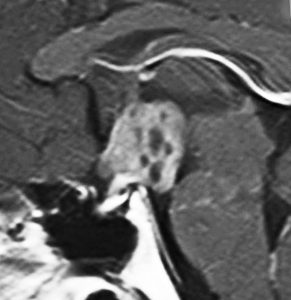

ICE化学療法投与開始から数日で小さくなります

この例は古いので第3脳室開窓術 ETV をしていません。左はICE化学療法前。中央は9日後。右は25日後です。閉塞性水頭症があっても1週間くらいで中脳水道が通って水頭症は改善します。ジャーミノーマであれば,ICE化学療法1コースでかなり縮小するはずです。このような顕著な効果がない時には,逆にジャーミノーマ以外の胚細胞腫瘍が混在していると考えた方がいいでしょう。多くは奇形腫の混在です。